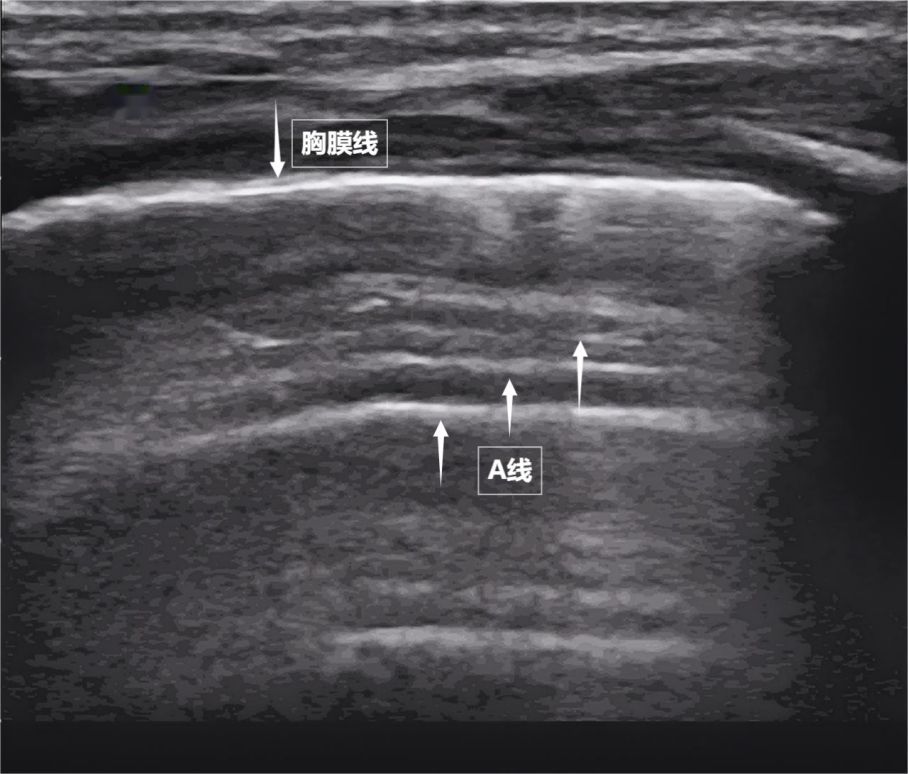

第一景:“海岸线与海浪”——胸膜线与A线

当声波穿过胸壁肋骨缝隙,首先会遇到紧贴肺表面的光滑薄膜——壁层胸膜和脏层胸膜。两者紧密相贴,中间没有多余的气体或液体。它们在屏幕上呈现为一条明亮、光滑的水平线,共同构成了胸膜线。这条线就是肺的“海岸线”。在它的下方,由于肺泡内大量气体对声波的强烈反射,会出现一系列与胸膜线平行的、等间距的、重复出现的明亮平行线,像海浪般不断向屏幕深处延伸,这就是A线( 见下图 )。A线是正常含气肺部的典型标志。它的存在直接提示肺表面含气充足,胸膜腔内无异常积液或气体。

图为正常新生儿肺部超声表现